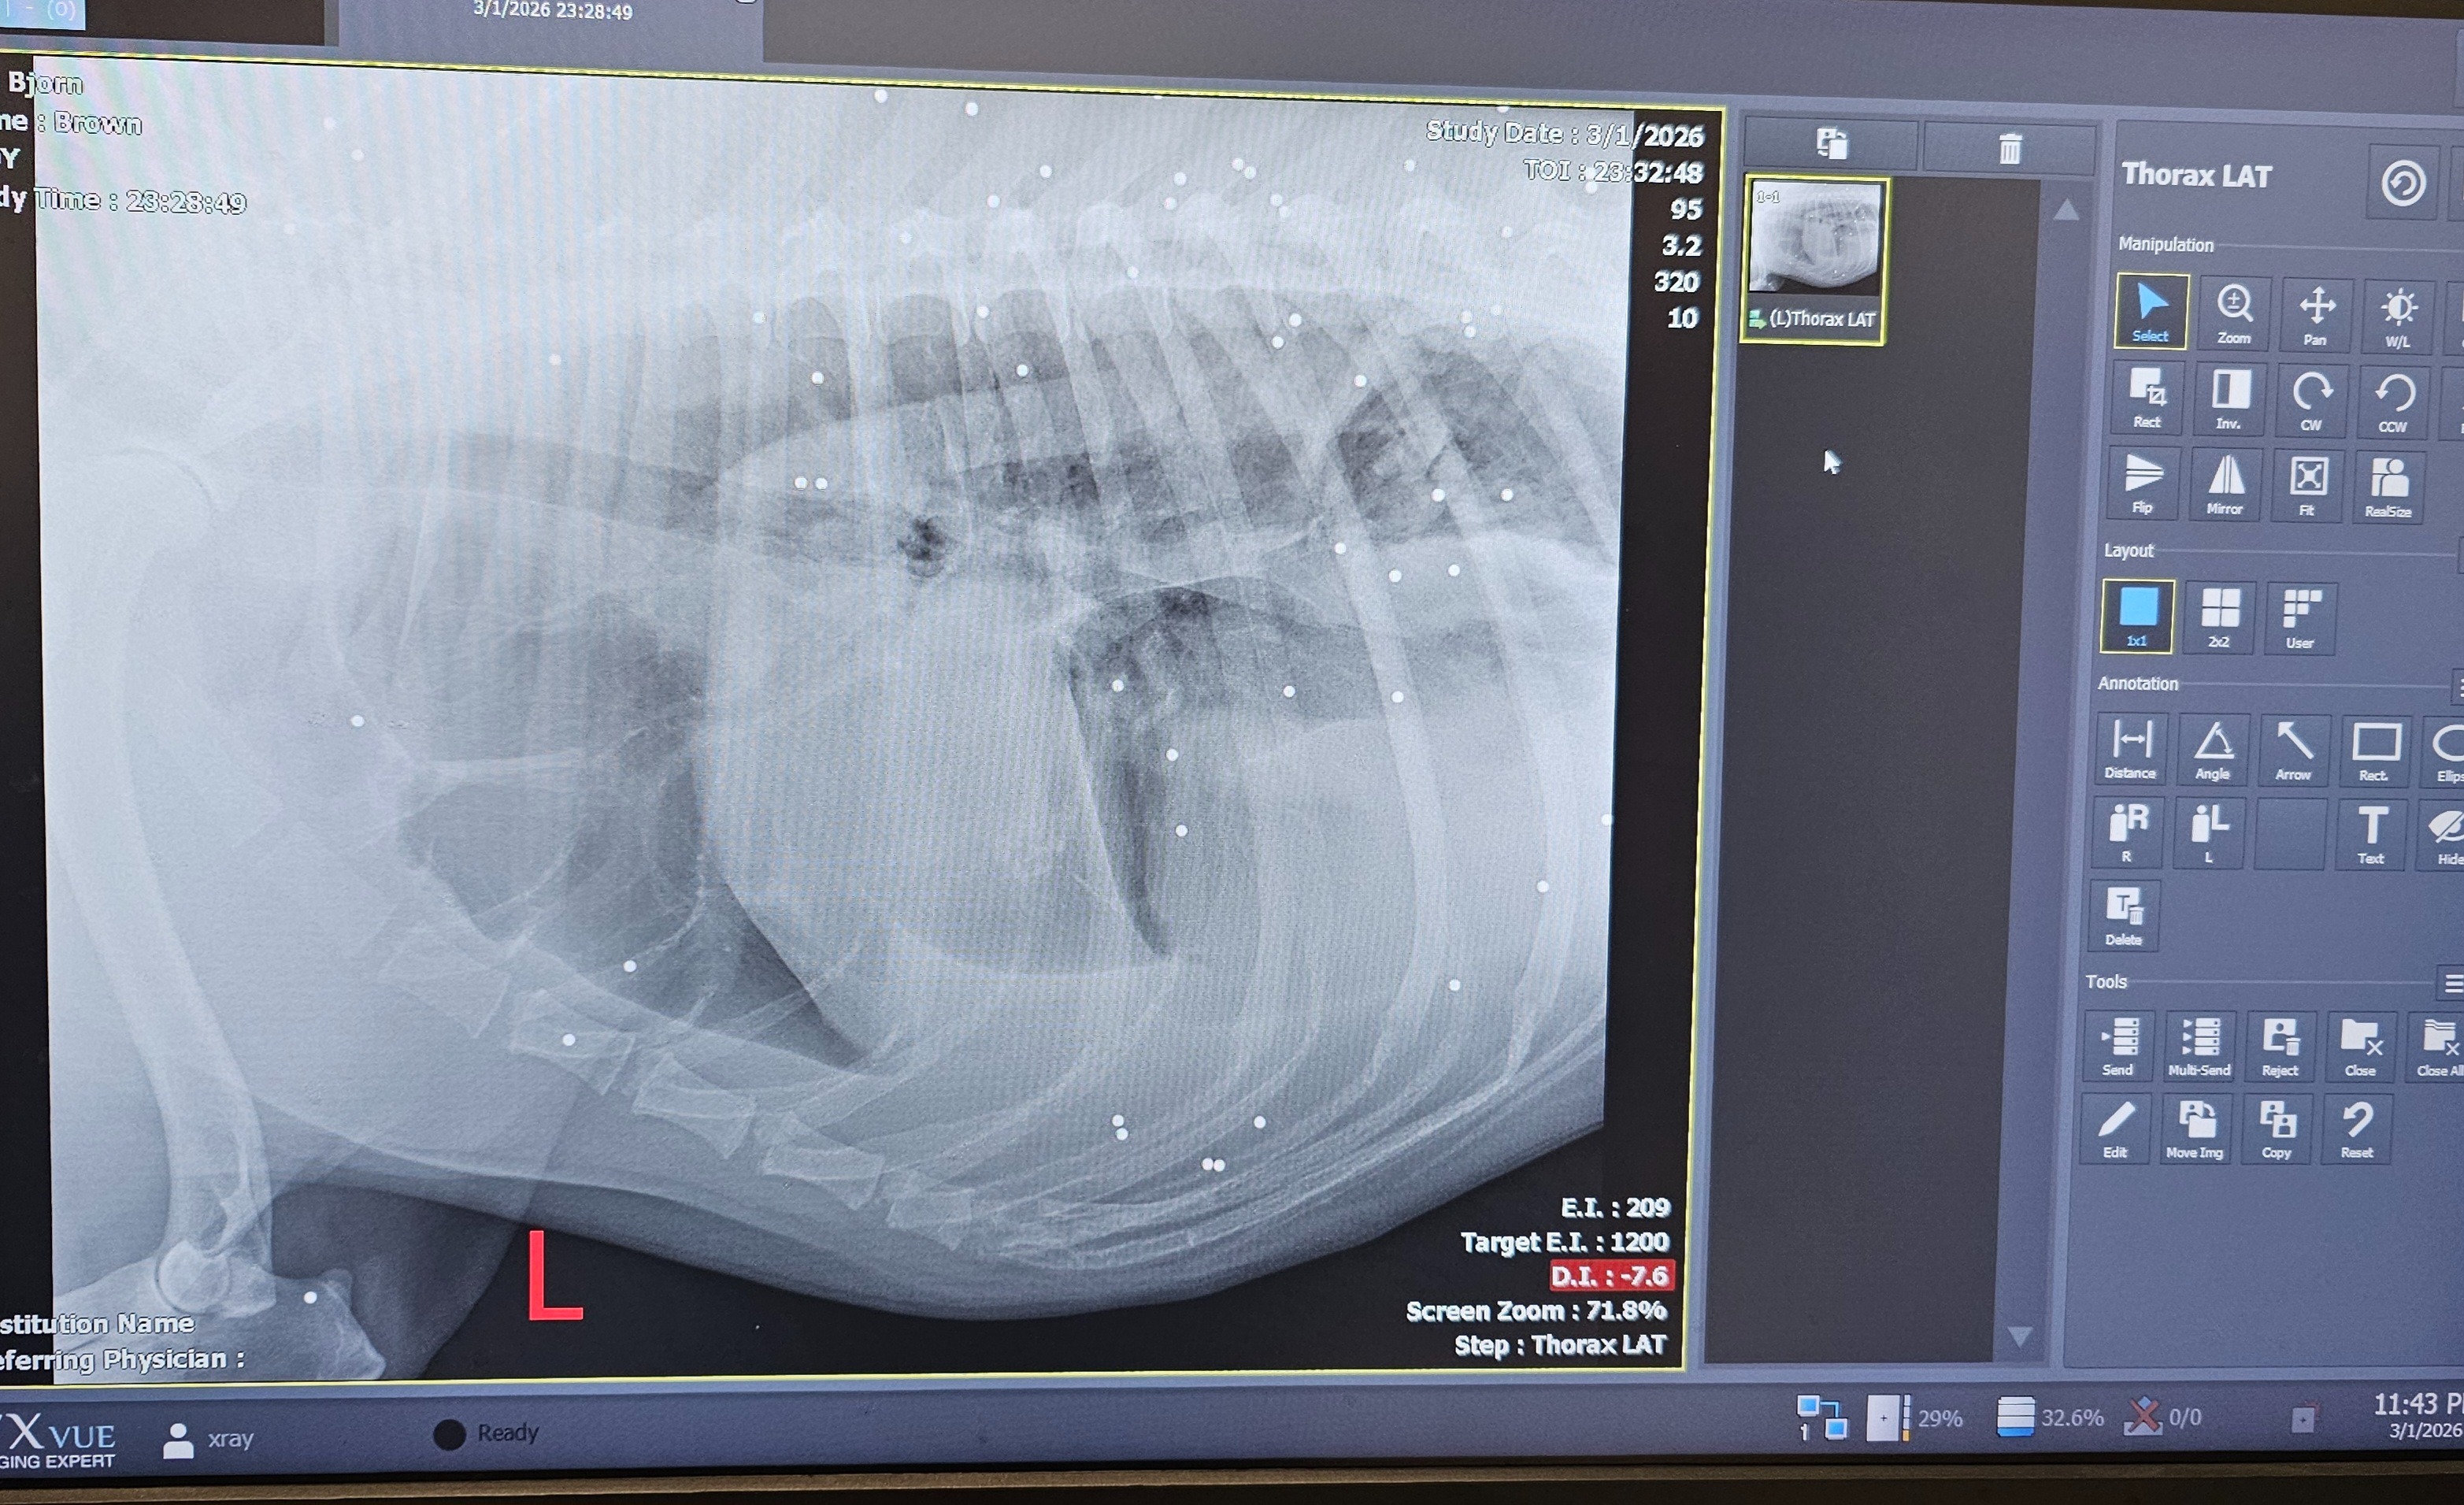

Our sweet Great Pyrenees, Bjorn, went missing from his kennel on Saturday. After hours of searching, he finally made his way back home — but something was terribly wrong. When I reached him, I realized he had been shot with a shotgun. I rushed him to Morgan Emergency Vet in Coos Bay, where the veterinarians discovered more than 30 pellets throughout his body. Bjorn was in shock, bleeding internally, and fighting to stay stable. Thanks to the incredible care he received overnight, the vet believes he can recover — but he will need ongoing medical treatment, monitoring, and follow-up care to make that possible.